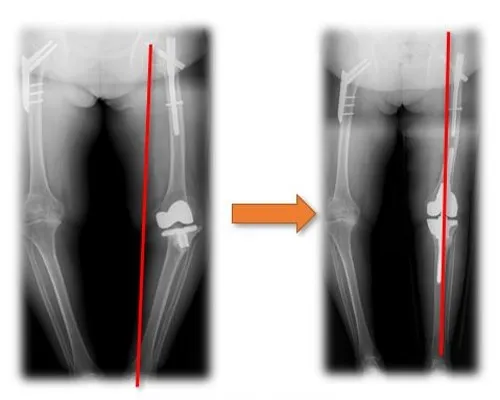

Clinical Application 1

Clinical Application 2